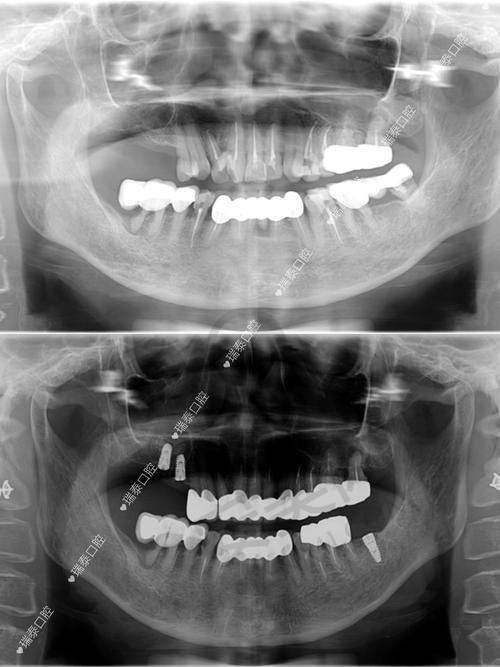

精细评估骨条件:通过CT检查精细评估骨条件是非常重要的。不同患者的牙槽骨情况不同,骨量、骨密度等因素都会影响种植牙的成功几率和成效。只有通过正确的评估,医生才能制定出更合适的治疗方案,选择更适合的种植体和治疗方式。